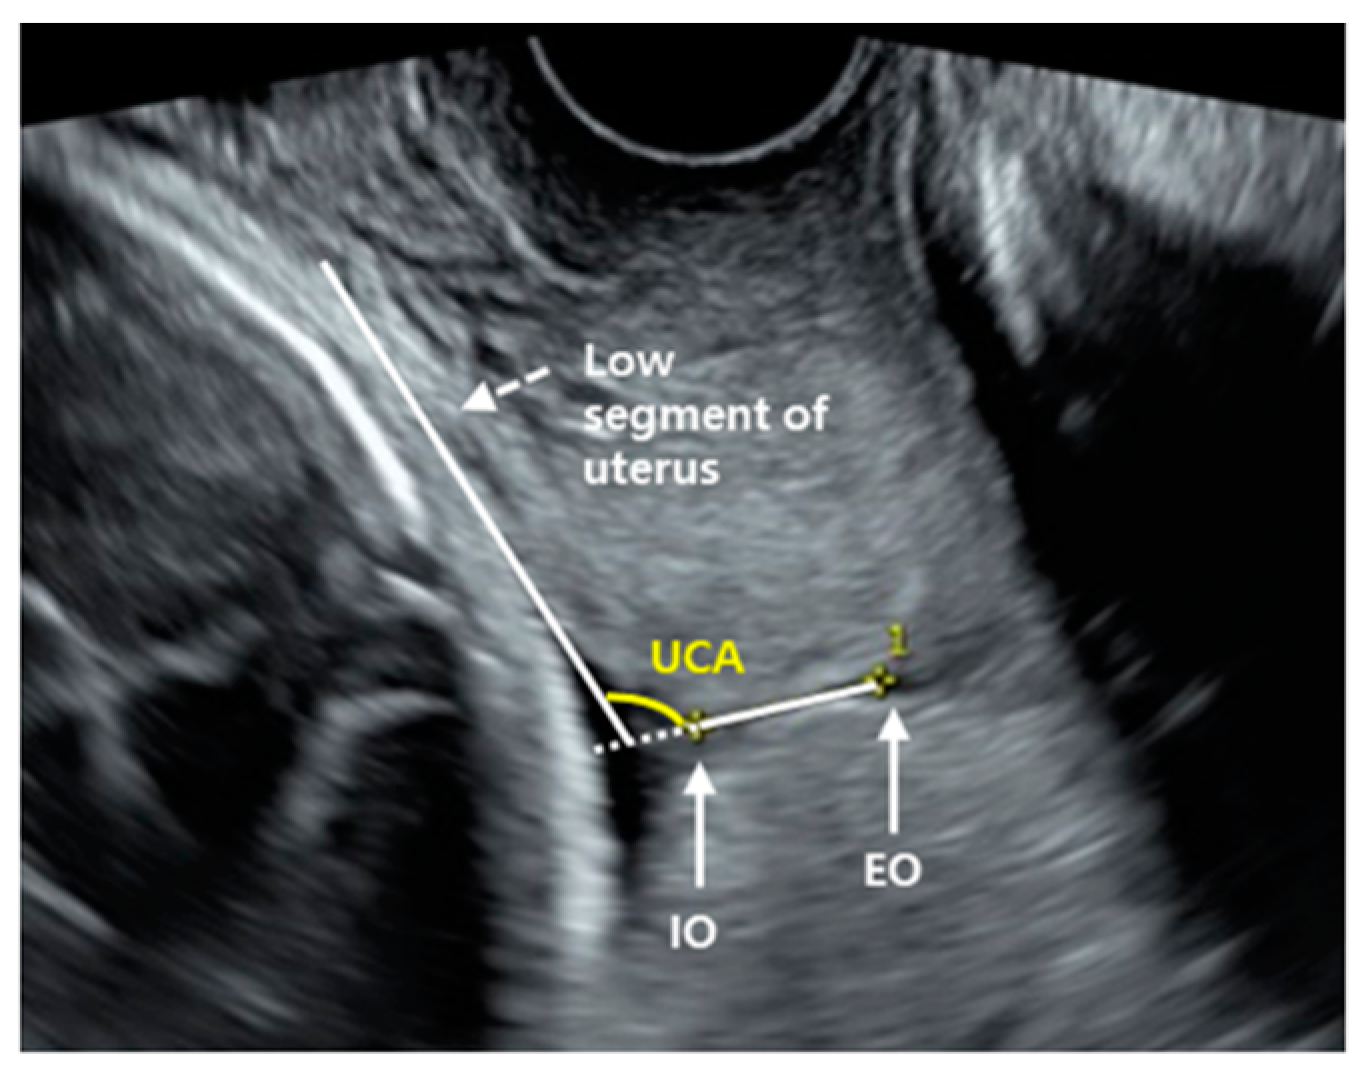

2.2. Uterocervical Angle Measurement